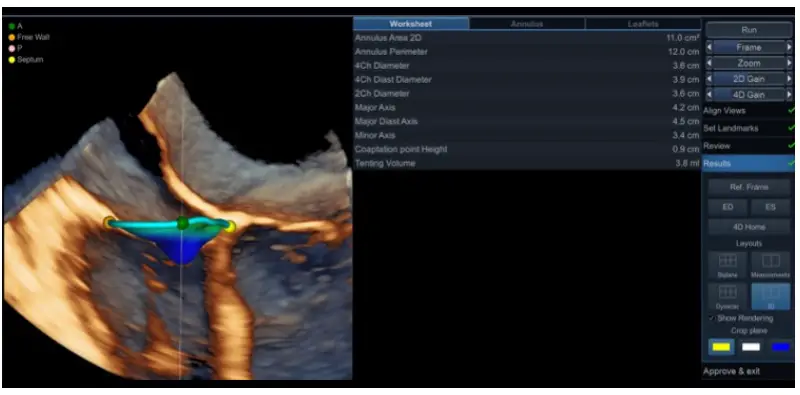

- Show Rendering and Crop plane options display the 4D rendered image together with the TV model, shown in different orientations: 4CH (yellow), 2CH (white) or SAX (blue) (Figure 9).

Figure 9. TV annulus and leaflets model superimposed on the 3D rendered 4-chamber view and the quantitative measurements of the leaflet geometry. - In case of inconsistencies between the TV model and the TV leaflets or annulus detected at this stage, or irregular contours of TV annulus model, go to the previous Review step for additional editing. You will be able to rotate and adjust the planes to identify the region requiring adjustments and you can use the red dot and the colorcoded TA landmarks to help orientation.

Figure 10. TV annulus and leaflets model superimposed on the 3D rendered 4-chamber view on transesophageal data set.